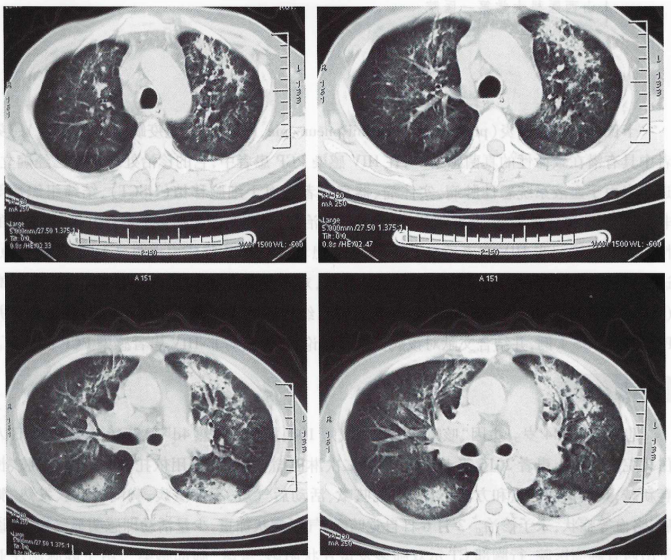

胸部CT(2016年2月6日)示双肺多发斑片状阴影(图1)。血常规(2016年2月9日,外院):WBC 21×109/L,PLT 423×109/L,NEU% 81%。血气分析(2016年2月10日,吸氧3 L/min):pH 7.43,PaO2 68 mmHg,PaCO2 37 mmHg,SaO98%,PaO2/FiO297 mmHg。

图1  2016年2月6日胸部CT:双肺多发斑片状阴影

2月15日患者气短症状突然较前加重,咳嗽、胸闷、气短明显,端坐呼吸。调整吸氧方式为储氧面罩吸氧,氧流量10 L/min,复查胸部CT提示以肺门为中心的双侧肺弥漫性磨玻璃及实变影(图2),病灶较2月6日明显加重。复查血气分析(储氧面罩吸氧,氧流量10 L/min):pH 7.518,PaCO2 30.8 mmHg,PaO2 49.3 mmHg,SaO2 86.4%,PaO2/FiO149 mmHg。

图2  2016年2月15日胸部CT:肺门为中心的双侧肺弥漫性磨玻璃及实变影

PJP患者的胸部CT多表现为双肺对称的磨玻璃影、实变影、马赛克征、碎石路征等征象。本病例2月15日胸部CT表现为典型的由肺门向周边放散的实变阴影(蝴蝶阴影),这对此后的临床明确诊断起到了非常大的提示作用,但具有上述影像学表现的患者仍需与药物性肺损伤、肺水肿、肺泡蛋白沉积症、急性间质性肺炎、弥漫性肺泡出血综合征、病毒性肺炎等相鉴别。